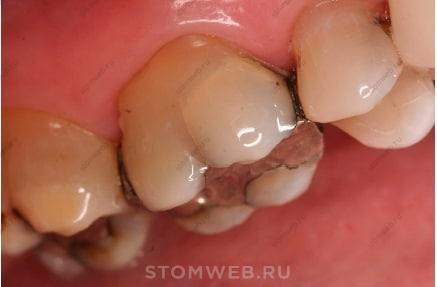

Коронка и корень являются не только местом начала, но и областью основного повреждения. На коронке (в большинстве случаев при распространении на корень) выделяют перелом бугра, перелом зуба и раскол зуба (Рис. 2 и 3);

Рис. 2. Перелом бугра. Перелом идет как в мезиодистальном, так и в вестибулооральном направлениях (пересекая краевой гребень, а также распространяясь вниз на вестибулярную или оральную борозду), часто встречается в зубах с обширными реставрациями. Он располагается на коронковой части зуба и может распространяться к цервикальному краю корня; при взгляде с проксимальной стороны перелом обычно не располагается центрально и идёт по боковой поверхности стенок, прилегающих к существующей реставрации. Важно отметить, что фрагменты зуба могут как отделяться (полный перелом), так и не отделяться (неполный перелом).

Переломы бугров зачастую присутствуют в зубах с широкими и/или глубокими реставрациями II класса или кариесом, который ослабил краевой гребень. Вышеперечисленные факторы снижают объём дентина, поддерживающего бугор, главным образом со стороны краевого гребня. Часто вовлечен один бугор с мезиодистальным и вестибулооральным направлением перелома (Рис. 1 и 6-9).

Рис. 6. Перелом бугра (полностью отделяемый перелом) с вскрытием пульпы. Обратите внимание на присутствие большой композитной реставрации.

Рис. 7. Перелом бугра (неотделяемый неполный перелом) определяется в виде изменения непрозрачности на вестибулярной поверхности мезиощёчного бугра. Обратите внимание на присутствие большой амальгамной реставрации.

Рис. 8. Перелом мезиолингвального бугра. (А) Линия перелома бугра начинается около дна полости на углу мезиооральной линии. (В) Перелом лучше визуализировался при использовании трансиллюминации. (С) После удаления реставрации было проведено зондирование пародонта в проксимальной части зуба (учитывались значения глубины в восьми точках).

Рис. 9. Перелом мезиолингвалього бугра. (А) Линия перелома бугра скрыта под реставрацией. (В) Удаление отделяемого фрагмента зуба на медиальной поверхности обнажило обширный кариес. (С) Удаление перелома мезиолингвального бугра показало, что перелом распространяется ниже десневого края и эпителиального прикрепления. (D) Удаленная часть зуба имеет большие размеры и усложняет лечение.

Поэтому, косой, раскалывающий перелом (Рис. 2) пересекает краевой гребень и продолжается вниз по вестибулярной или язычной бороздке, часто в пришеечную область на уровне или апикальнее края десны и эпителиального прикрепления, зачастую не распространяясь дальше цервикальной трети зуба. Если вовлечены два бугра, линии перелома будут проходить в медиальном и дистальном направлениях без вовлечения вестибулярного или язычного компонента. Обычно пульпа не обнажается, особенно в зубах пожилых людей с маленькими пульпарными камерами.

В отличие от перелома зуба (будет обсуждаться дальше), перелом бугра зачастую не проходит по середине окклюзионной или проксимальной поверхностях (Рис 2.). Реставрация сама по себе может “скрывать” перелом бугра (Рис. 9). В таком случае используется зонд для проверки места прилегания реставрации к тканям зуба на предмет присутствия отделяющихся фрагментов. Бывают случаи, когда трещина бугра присутствует как без отделяемого фрагмента зуба (Рис. 7), так с явным отделением (Рис. 6).